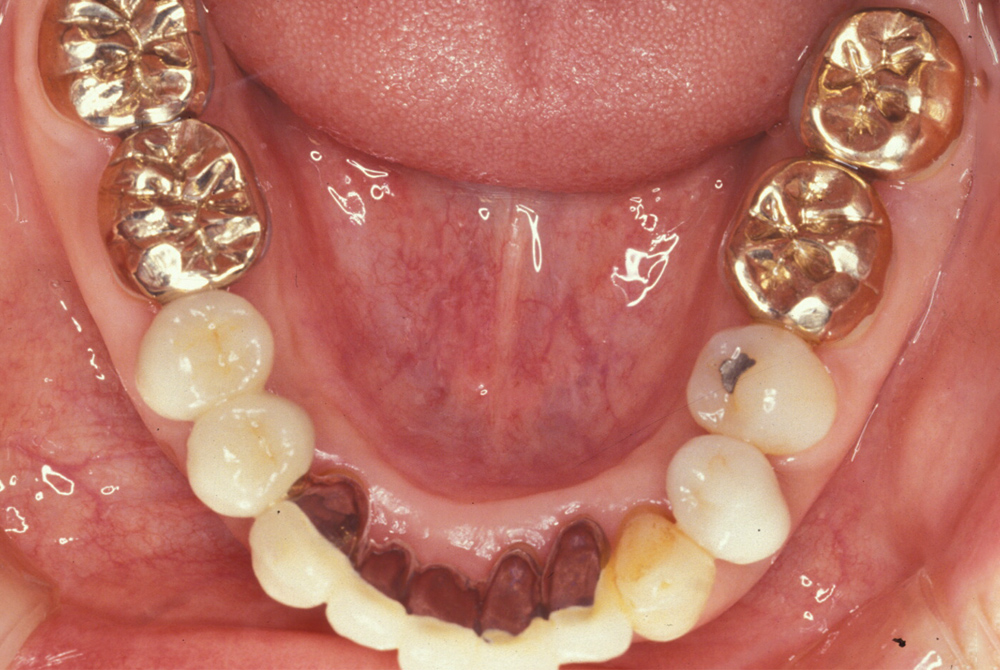

- 治療前 - 10年くらい前から、歯茎がたびたび腫れていたが、歯医者に行くのが怖くてずっと放置していた。最近は、下の前歯がグラグラして噛めないし、めまいや頭痛などの更年期障害もおこってきたので、思い切って来院した。 - 治療後 - 患者さんのお話をお伺いしたところ、入れ歯ではなく、ご自分の歯でかめるようになりたいという強いご希望があることがわかりましたので、全体的に歯周病の根治術を行い、ブラッシングがしやすくなるようにとの観点から歯並びの矯正治療を行いました。 何本かはどうしても抜歯しなくてはなりませんでしたが、2年以上の治療期間をとおして何とか固定式の歯を入れることができました。